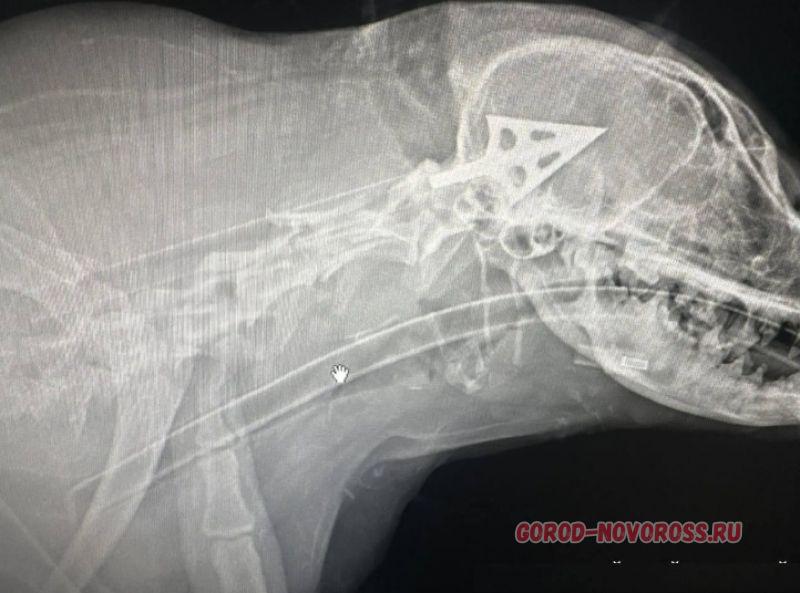

В понедельник, 23 марта, жители Цемдолины и Борисовки наблюдали страшную картину: рыжая собака бегала по улицам со стрелой в боку.

Волонтеры искали несчастное животное два дня, и только вчера к вечеру им удалось обнаружить раненого пса.

Когда я увидела в чате фото собаки со стрелой в боку, я выехала в Цемдолину, район ГСК по ул.Тепличная/ Мятная. Со мной в спасении участвовала Наталья Савельева, она оказывает помощь бездомным животным («Лучик надежды»).

Соседи рассказали нам, что это уже не первый случай, когда в округе находили собак, умерших от ранения стрелами. Стрела арбалетная, тяжелая. У нашей дворняги, в ветклинике ее назвали Булкой, было три входных отверстия.

Эту собаку все в районе Тепличной/Мятной знали и подкармливали. Она была чипирована, не проявляла никакой агрессии к людям, даже боялась их. Видимо, не зря…

Булка выжила и чувствует себя удовлетворительно. Наталья Манина сообщила «Новороссийскому рабочему», что она подала заявление о жестоком обращении с животными в УВД Приморского района. Заявление принято, правоохранители начали поиск стрелка.